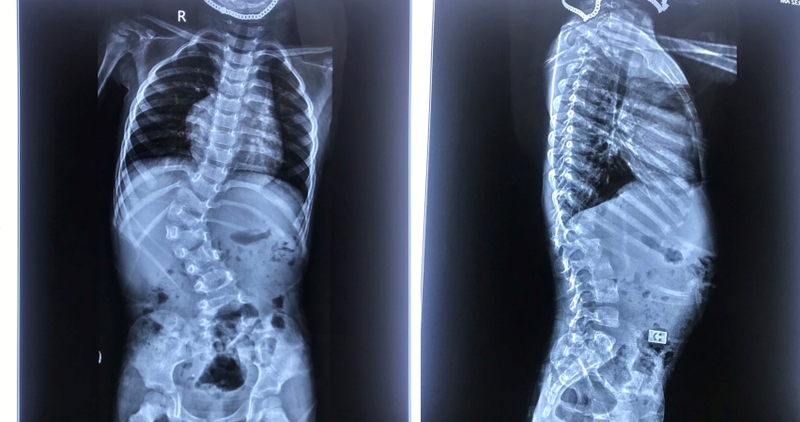

Ở trạng thái bình thường, cột sống khi nhìn ngang sẽ tạo thành một đường cong uyển chuyển, ngửa ra trước ở đoạn cổ, cong ra sau ở đoạn lưng. Tại vị trí thắt lưng, ưỡn nhẹ ra trước và cùng xương cùng cụt tạo thành một khối cong ra phía sau. Còn khi nhìn thẳng sẽ thấy cột sống là một đường thẳng từ đỉnh đầu xuống đỉnh xương cùng cụt.

Vẹo cột sống là khái niệm chỉ tình trạng cột sống bị cong, vẹo bất thường. Tùy vào nguyên nhân, dấu hiệu vẹo cột sống có thể dễ dàng nhìn thấy như cột sống lệch sang một bên, đổ về phía trước hoặc phía sau (gù cột sống), cột sống lệch sang một bên (cong cột sống).